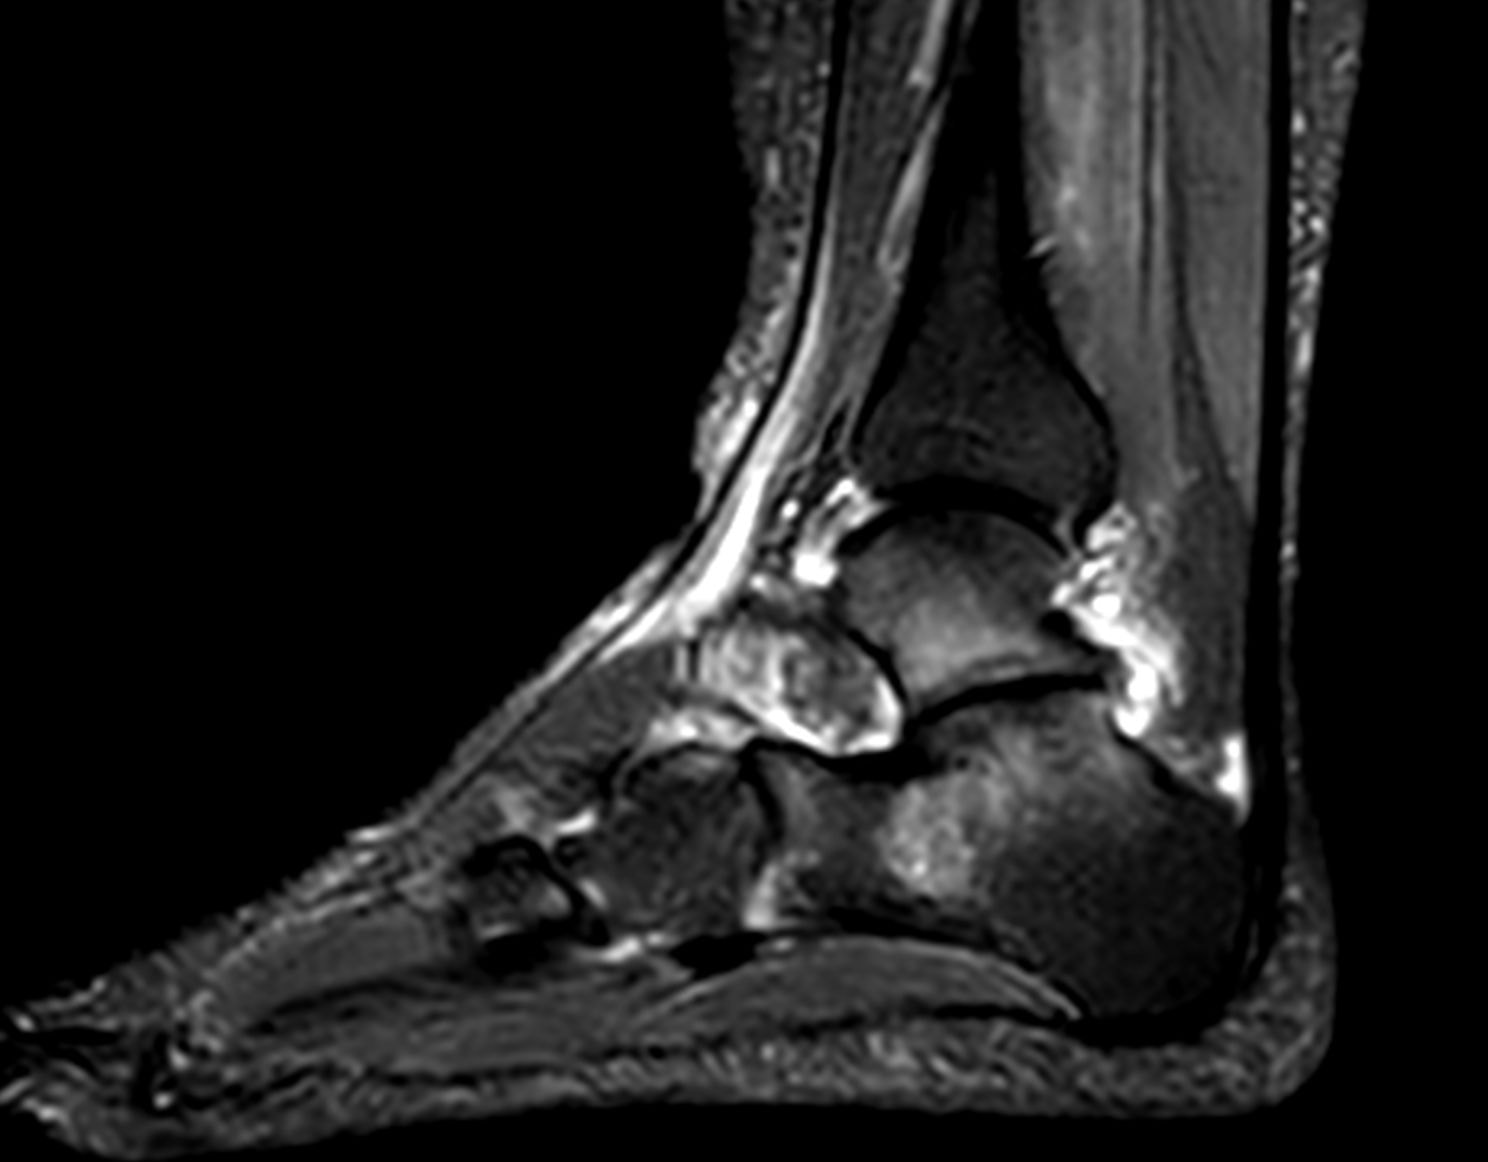

Το οστικό οίδημα συνήθως προκαλεί βαθύ πόνο μέσα στην άρθρωση ή σε συγκεκριμένο σημείο του οστού, ιδιαίτερα όταν φορτίζετε το πόδι, ανεβαίνετε σκάλες, περπατάτε για ώρα ή αυξάνεται συνολικά η δραστηριότητα μέσα στην ημέρα. Πολλοί το περιγράφουν σαν «βαρύ» πόνο ή σαν μια ενόχληση που δεν μοιάζει με επιφανειακό μυϊκό τραυματισμό.

Σε ορισμένες περιπτώσεις μπορεί να υπάρχει αίσθημα πίεσης, ευαισθησία στο βάθος της περιοχής και δυσκολία σε κινήσεις που μέχρι πριν ήταν απλές. Όταν το πρόβλημα αφορά γόνατο, ποδοκνημική ή ισχίο, είναι συχνό να αλλάζει ασυναίσθητα και ο τρόπος που περπατάτε ώστε να προστατεύσετε το σημείο που ενοχλεί.